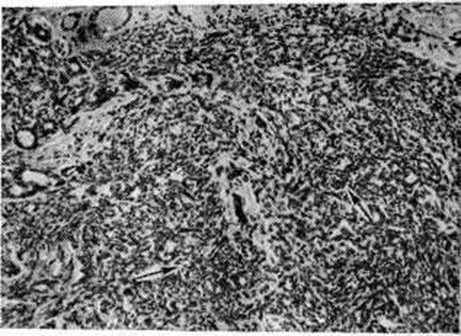

Рис. 3.

Микропрепарат молочной железы при склерозирующем аденозе: разрастания миоэпителиальных клеток указаны стрелками; окраска гематоксилинэозином; × 100.

Особой разновидностью эпителиальной пролиферации при Мастопатия является склерозирующий аденоз. В так называемый цветущей фазе склерозирующего аденоза обнаруживаются очаги выраженной пролиферации эпителия ацинусов и миоэпителия (рисунок 3); образуются сплошные поля из мелких трубочек, тяжей, альвеол, лежащих в умеренно развитой строме. Постепенно процесс переходит в фиброзную фазу, при которой в полях гиалинизированной соединительной ткани сохраняются лишь отдельные, чаще всего тубулярные структуры, симулирующие в некоторых случаях гистологический картину инфильтративного рака. При пролиферативной Мастопатия выявляются также очаги фиброэпителиальной пролиферации с образованием мелких фиброаденом и цистаденопапиллом. Для цистаденопапиллом характерно формирование в протоках различной величины соединительнотканных сосочков, покрытых несколькими рядами цилиндрического или кубического эпителия (рисунок 4). В крупных протоках могут формироваться отдельные цистаденопапилломы , приобретающие самостоятельное клинические, значение.